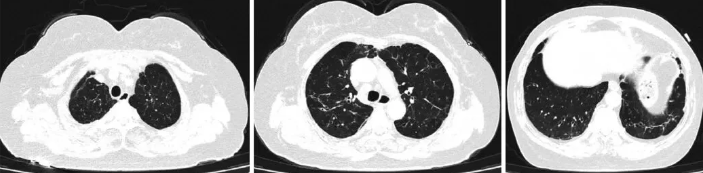

该患者出院后给予口服强的松30 mg qd,羟氯奎200 mg bid,半个月后(2024-08-07)在我院门诊复诊,药物减量为强的松25 mg qd,羟氯奎200 mg bid。2024-09-04患者复查胸部CT等后(图4)调整为强的松15 mg qd,羟氯奎200 mg bid。2024-10-09患者复诊后药物调整为强的松10 mg qd,羟氯奎200 mg bid。截至投稿时,该患者未再出现咳嗽、咳痰,指脉氧维持在98%~99%左右。

图4 患者2024年出院后胸部CT像(随访)

两肺见斑片状、索条状高密度影,部分周围见囊状、柱状支气管影;纵隔淋巴结稍大;两侧胸膜增厚;较2024-07-11部分吸收。